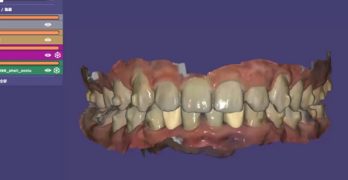

Cómo mejorar los resultados de la Ortodoncia de Alineadores con auxiliares creativos y tecnológicos

No se nos olvidan los alineadores, no se nos olvida. Y por lo mismo les traemos un artículo llamado Customized adjuncts … [Leer más...] acerca de Cómo mejorar los resultados de la Ortodoncia de Alineadores con auxiliares creativos y tecnológicos